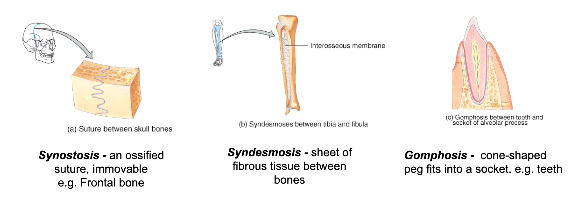

what is a synostosis fibrous joint? [1]

whats a bone with an example of a synostosis joint? [1]

what is a syndemosis fibrous joint? [1]

whats a bone with an example of where find a syndemosis joint? [1]

what is a gomphosis fibrous joint? [1]

whats a bone with an example of where find a gomphosis joint? [1]

what is a synostosis fibrous joint? [1]

At some sutures, the connective tissue will ossify and be converted into bone, causing the adjacent bones to fuse to each other (and make one big bone)

whats a bone with an example of a synostosis joint? [1]

frontal bone

what is a syndemosis fibrous joint? [1]

sheet of fibrous tissue between bones = interosseous membrane

whats a bone with an example of where find a syndemosis joint? [1]

between radius and ulnar / between tibia and fibula

what is a gomphosis fibrous joint? [1]

cone shaped peg fits into a socket

whats a bone with an example of where find a gomphosis joint? [1]

teeth